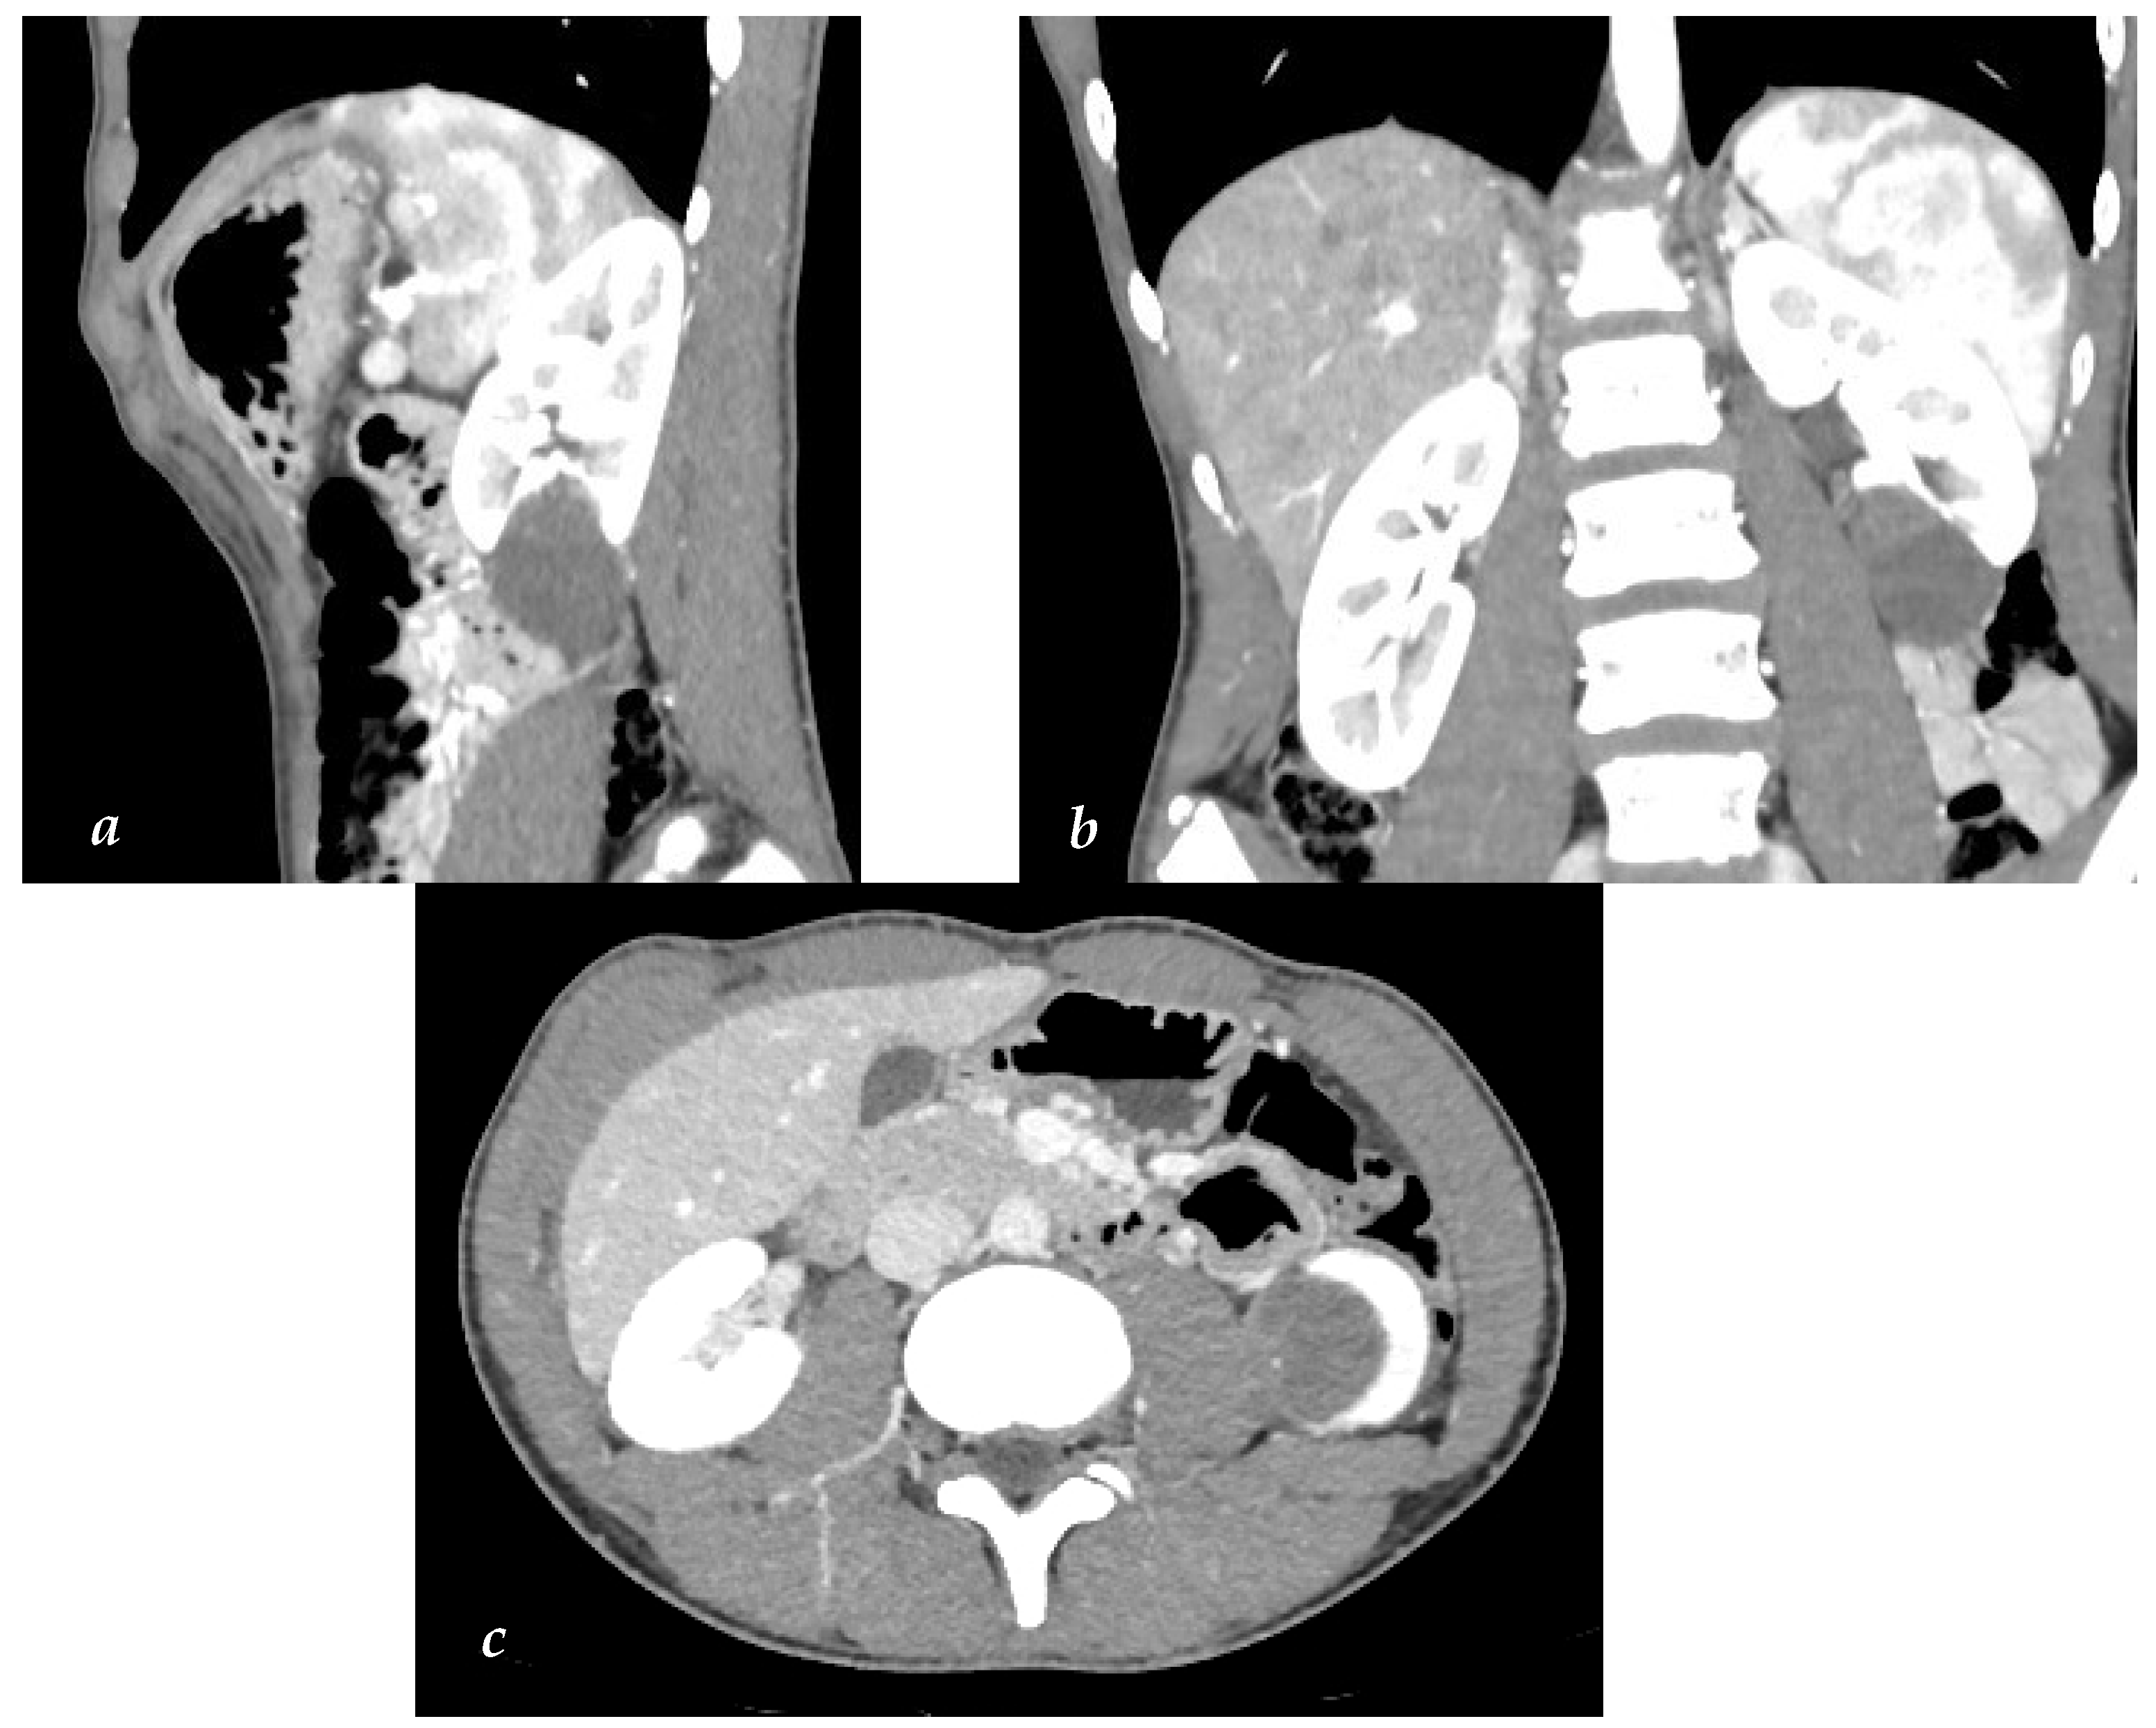

A 14-year-old boy with a left varicocele underwent an abdominal US (not recommended by the EAU/ ESPU guidelines), which incidentally revealed a hyperechoic round mass in the lower pole of the left kidney measuring 35 × 33 mm. Abdominal low-dose CT confirmed a partially exophytic lesion in the lower pole of the left kidney. The lesion exhibited a hypodense lower part suggestive of liquid content without contrast enhancement and a solid upper part with point-like calcifications and contrast enhancement. It was classified as a Bosniak III cyst (Figure 1a,b).

Figure 1. (ac) Abdominal CT images. (a) Sagittal view of the cleavage plane between the cyst and renal parenchyma conceivable. (b) Coronal view of tumor relationships with adjacent organs. (c) Transverse view with no signs of invasion of the surrounding organs.